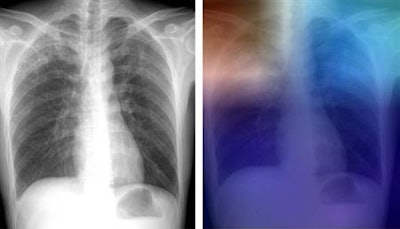

Artificial intelligence (AI) software can accurately identify tuberculosis (TB) on chest radiographs, offering the potential to serve as an inexpensive or even free method to screen for the often deadly disease in underserved countries, according to a study published online April 25 in Radiology.

A research team from Thomas Jefferson University Hospital in Philadelphia found that a combination of two types of an artificial intelligence algorithm called a deep convolutional neural network could detect tuberculosis with 96% accuracy. What's more, the group determined that performance could be improved even further if a cardiothoracic radiologist read the few cases that had discordant results on the two AI models.

To train the neural networks to learn to how to detect TB, the researchers used 685 posteroanterior chest radiographs that were assembled from four sources of data: two publicly available datasets from the U.S. National Institutes of Health (NIH), a dataset from Thomas Jefferson University, and a dataset from the Belarus Tuberculosis Portal.